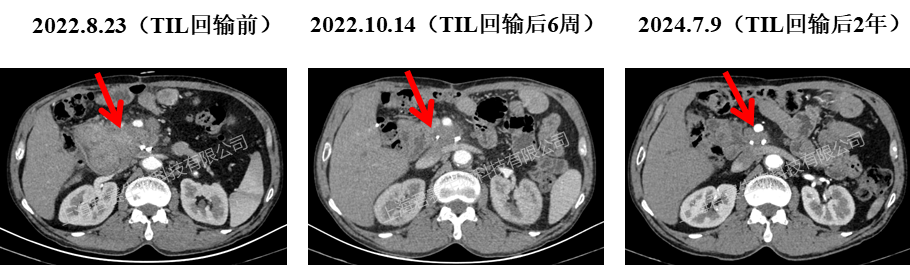

国内突破:

临床中已证实可实现肿瘤显著缩小、仅一次用药即可长期有效,同时凭借温和的治疗方案,让更多身体状况较差的晚期患者能够耐受并从中获益。